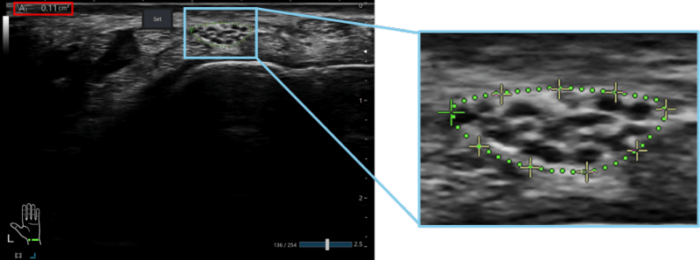

これに対し、本機能では画像を静止した後に計測ボタンを押下するだけで、AIが神経領域を認識し、断面積が算出される(Fig. 2b)。計測結果として画面上に神経領域の輪郭と断面積の数値が表示され、医師はその結果を確認できる(Fig. 3)。計測結果が適切であることを確認したうえで、必要に応じて画面上に配置された制御点(Fig.3 右図の十字点)をタッチ操作で動かすことで簡便に輪郭を微調整できる。制御点の間隔は指の幅よりも広くなるように設計しており、タッチ操作にストレスを生じにくいよう工夫している。

写真

Fig.3 自動計測された神経領域の輪郭(緑点線)と断面積の数値(赤枠内)の表示例